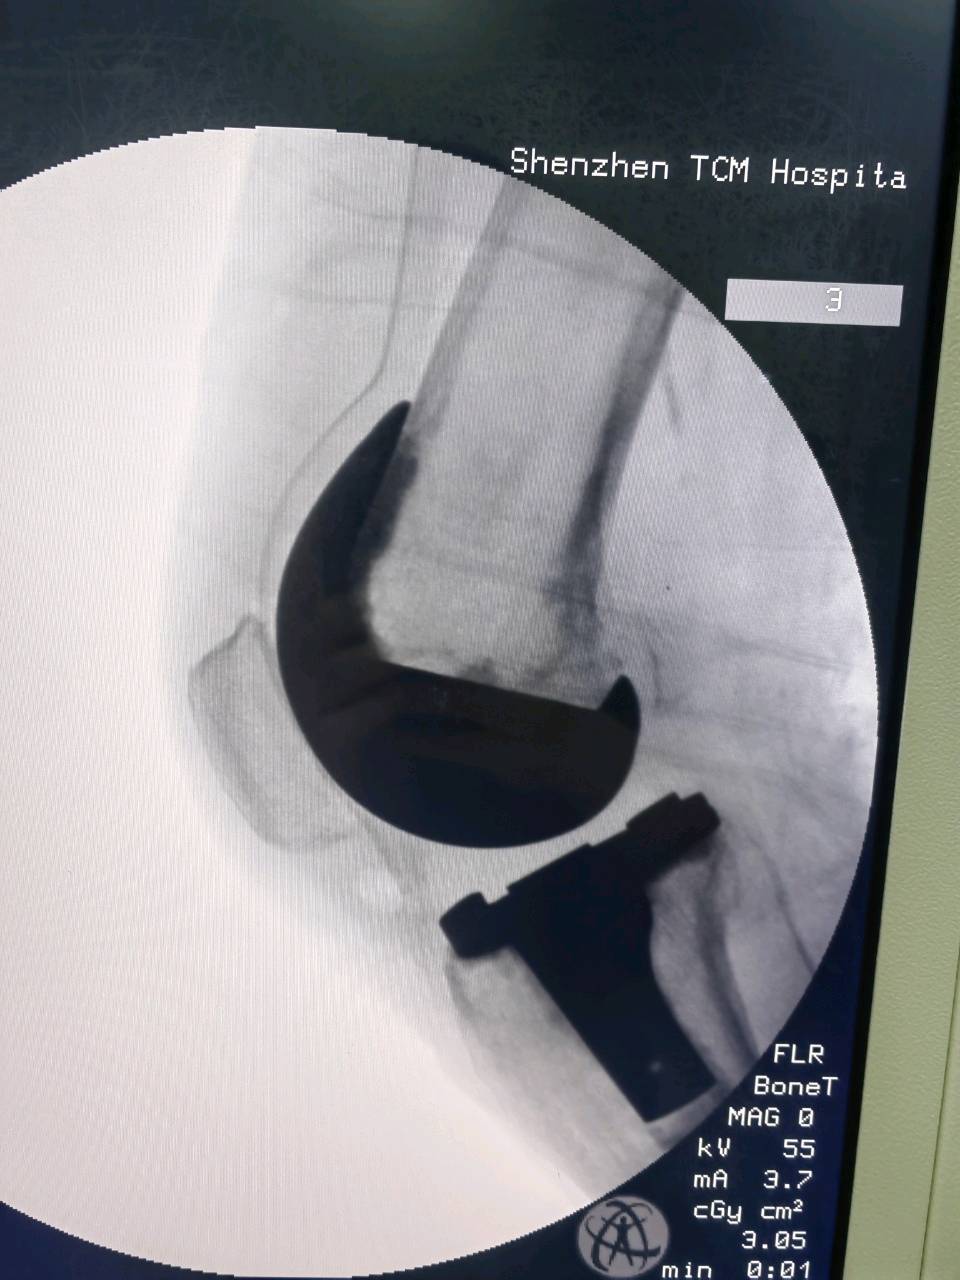

· 术前会通过X光、CT或MRI进行精确的评估和测量,术中会使用工具(甚至机器人辅助)来确保假体安装的精准度,从而保证膝关节的力线和活动度。

· 精准医疗: 基于患者解剖结构的“个性化截骨工具”和“机器人辅助手术”正在推广应用,让手术更加精准,效果更可预测。